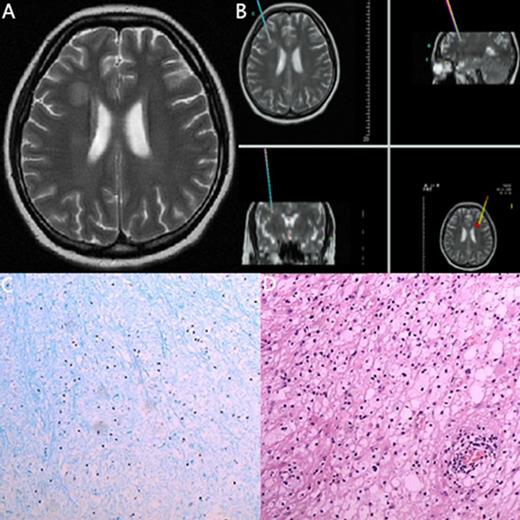

| 9 | 49/M | ALL (B cell) | 49/1 mo after chemo | none | MRI: Glial cell proliferation around lesion at right parietal lobe. | Leukemia | Glial cell hyperplasia | Improved | |